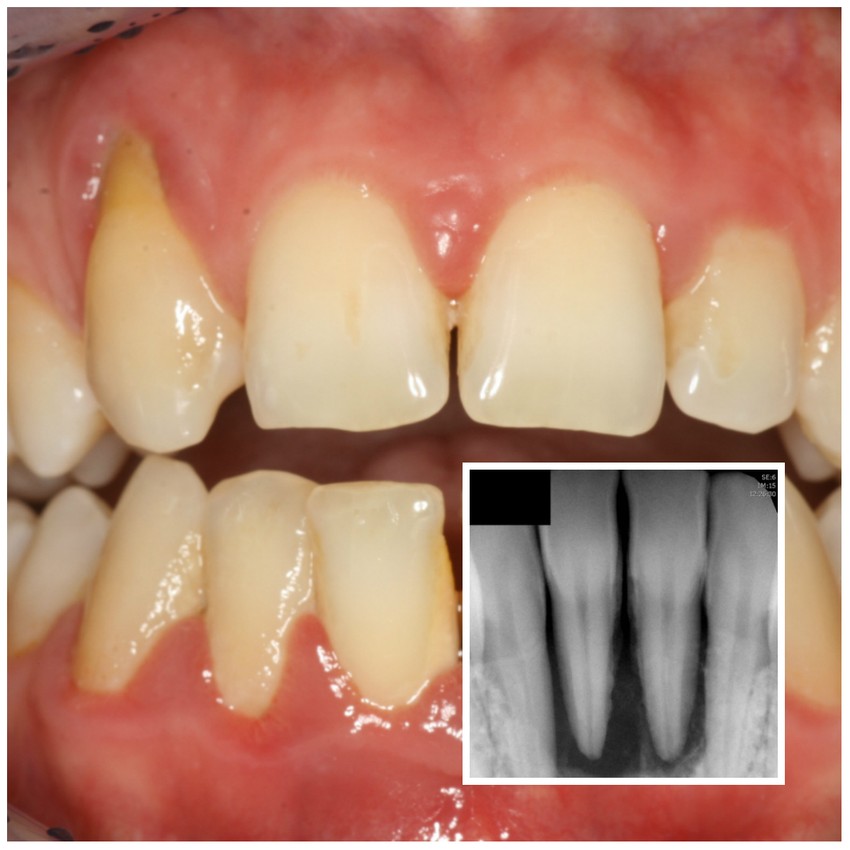

Regeneratív tasakműtét eredménye